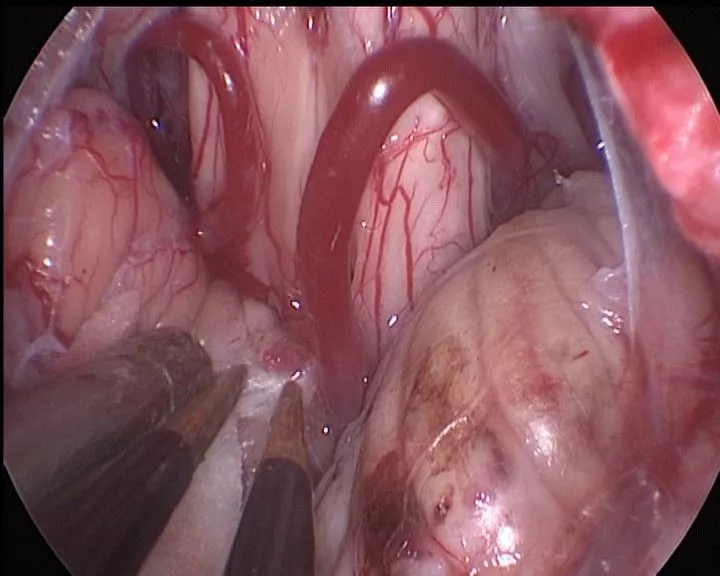

分离小脑谷,寻找四脑室正中孔

暴露四脑室正中孔,可见增厚的脉络膜

明胶海绵放入正中孔,分隔脑干和脉络膜

电凝并切开增厚的脉络膜

完全开放四脑室正中孔